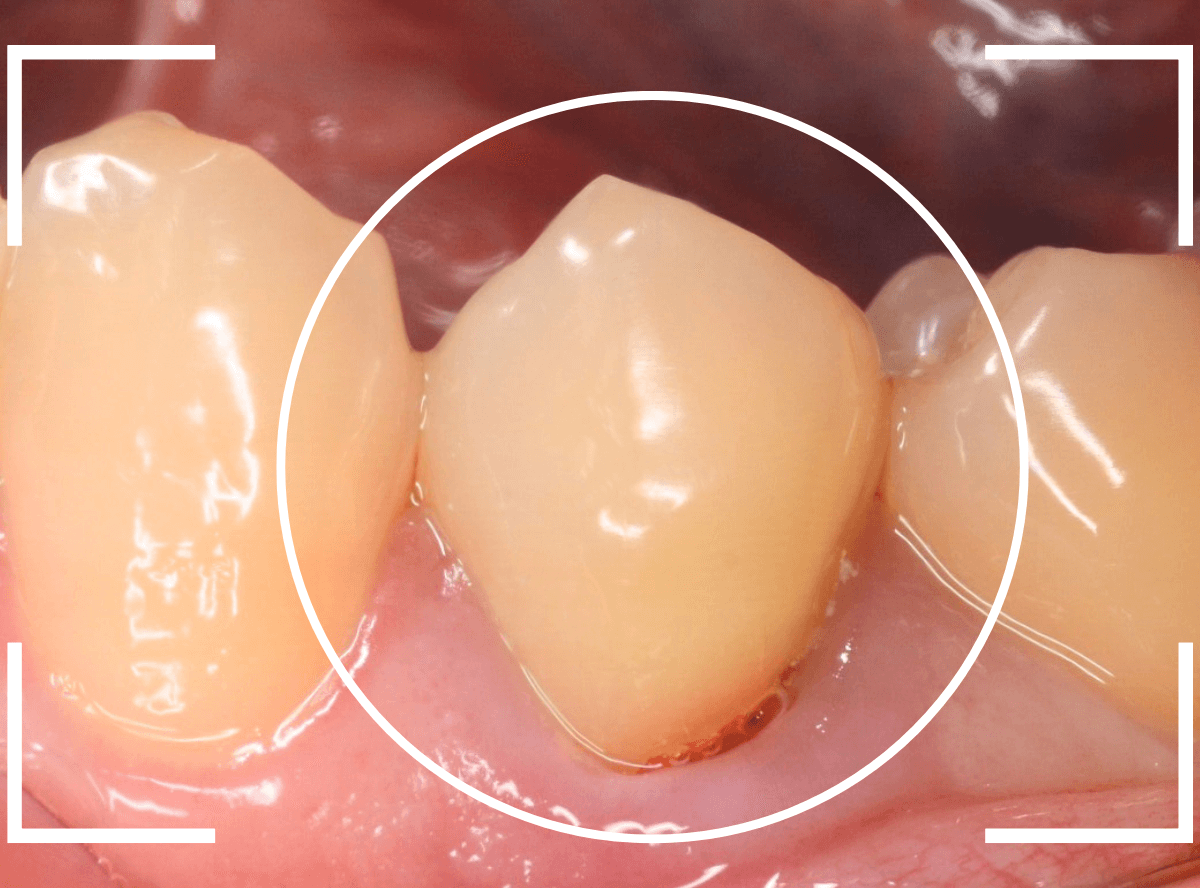

「歯がとても痛む」という患者さんが来院されました。

初見では、特に大きな虫歯や歯周病という感じではありませんでした。

しかし、ピンセットで歯を叩くと、確実にこの歯で反応があります。

レントゲン写真でも、大きな虫歯などはなさそうな感じです。

もう一度歯を確認すると、つけ根がうっすらと虫歯っぽいです。

これかな?しかし、風をかけてもしみません。

うーん。。。